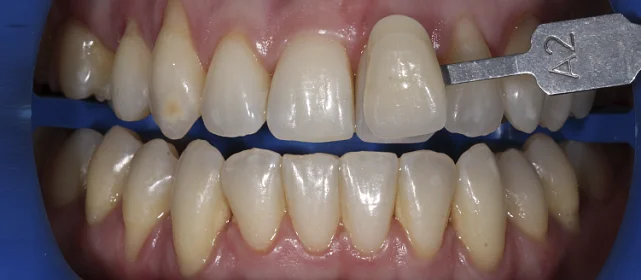

Нарушение соотношения челюстей и неправильное положение зубов — зубные ряды смыкались некорректно, зубы стояли со смещением.

Проблема: В клинику обратился мужчина с жалобами на неправильное положение зубов и смыкание — ряды сходились некорректно, зубы стояли со смещением. При этом было важно, чтобы лечение оставалось незаметным для окружающих, поэтому вариант с брекетами не рассматривался.

Решение: Поставили элайнеры Invisalign на обе челюсти. Лечение заняло 4 года — случай потребовал нескольких этапов коррекции, каждый из которых последовательно приближал зубы к нужному положению. Капы менялись каждые 1–2 недели, контрольные визиты — для отслеживания прогресса и выдачи новых наборов. Зубы встали на место, смыкание пришло в норму. Зафиксировали ретейнеры на обе челюсти, пациент направлен к ортопеду для завершающего этапа.